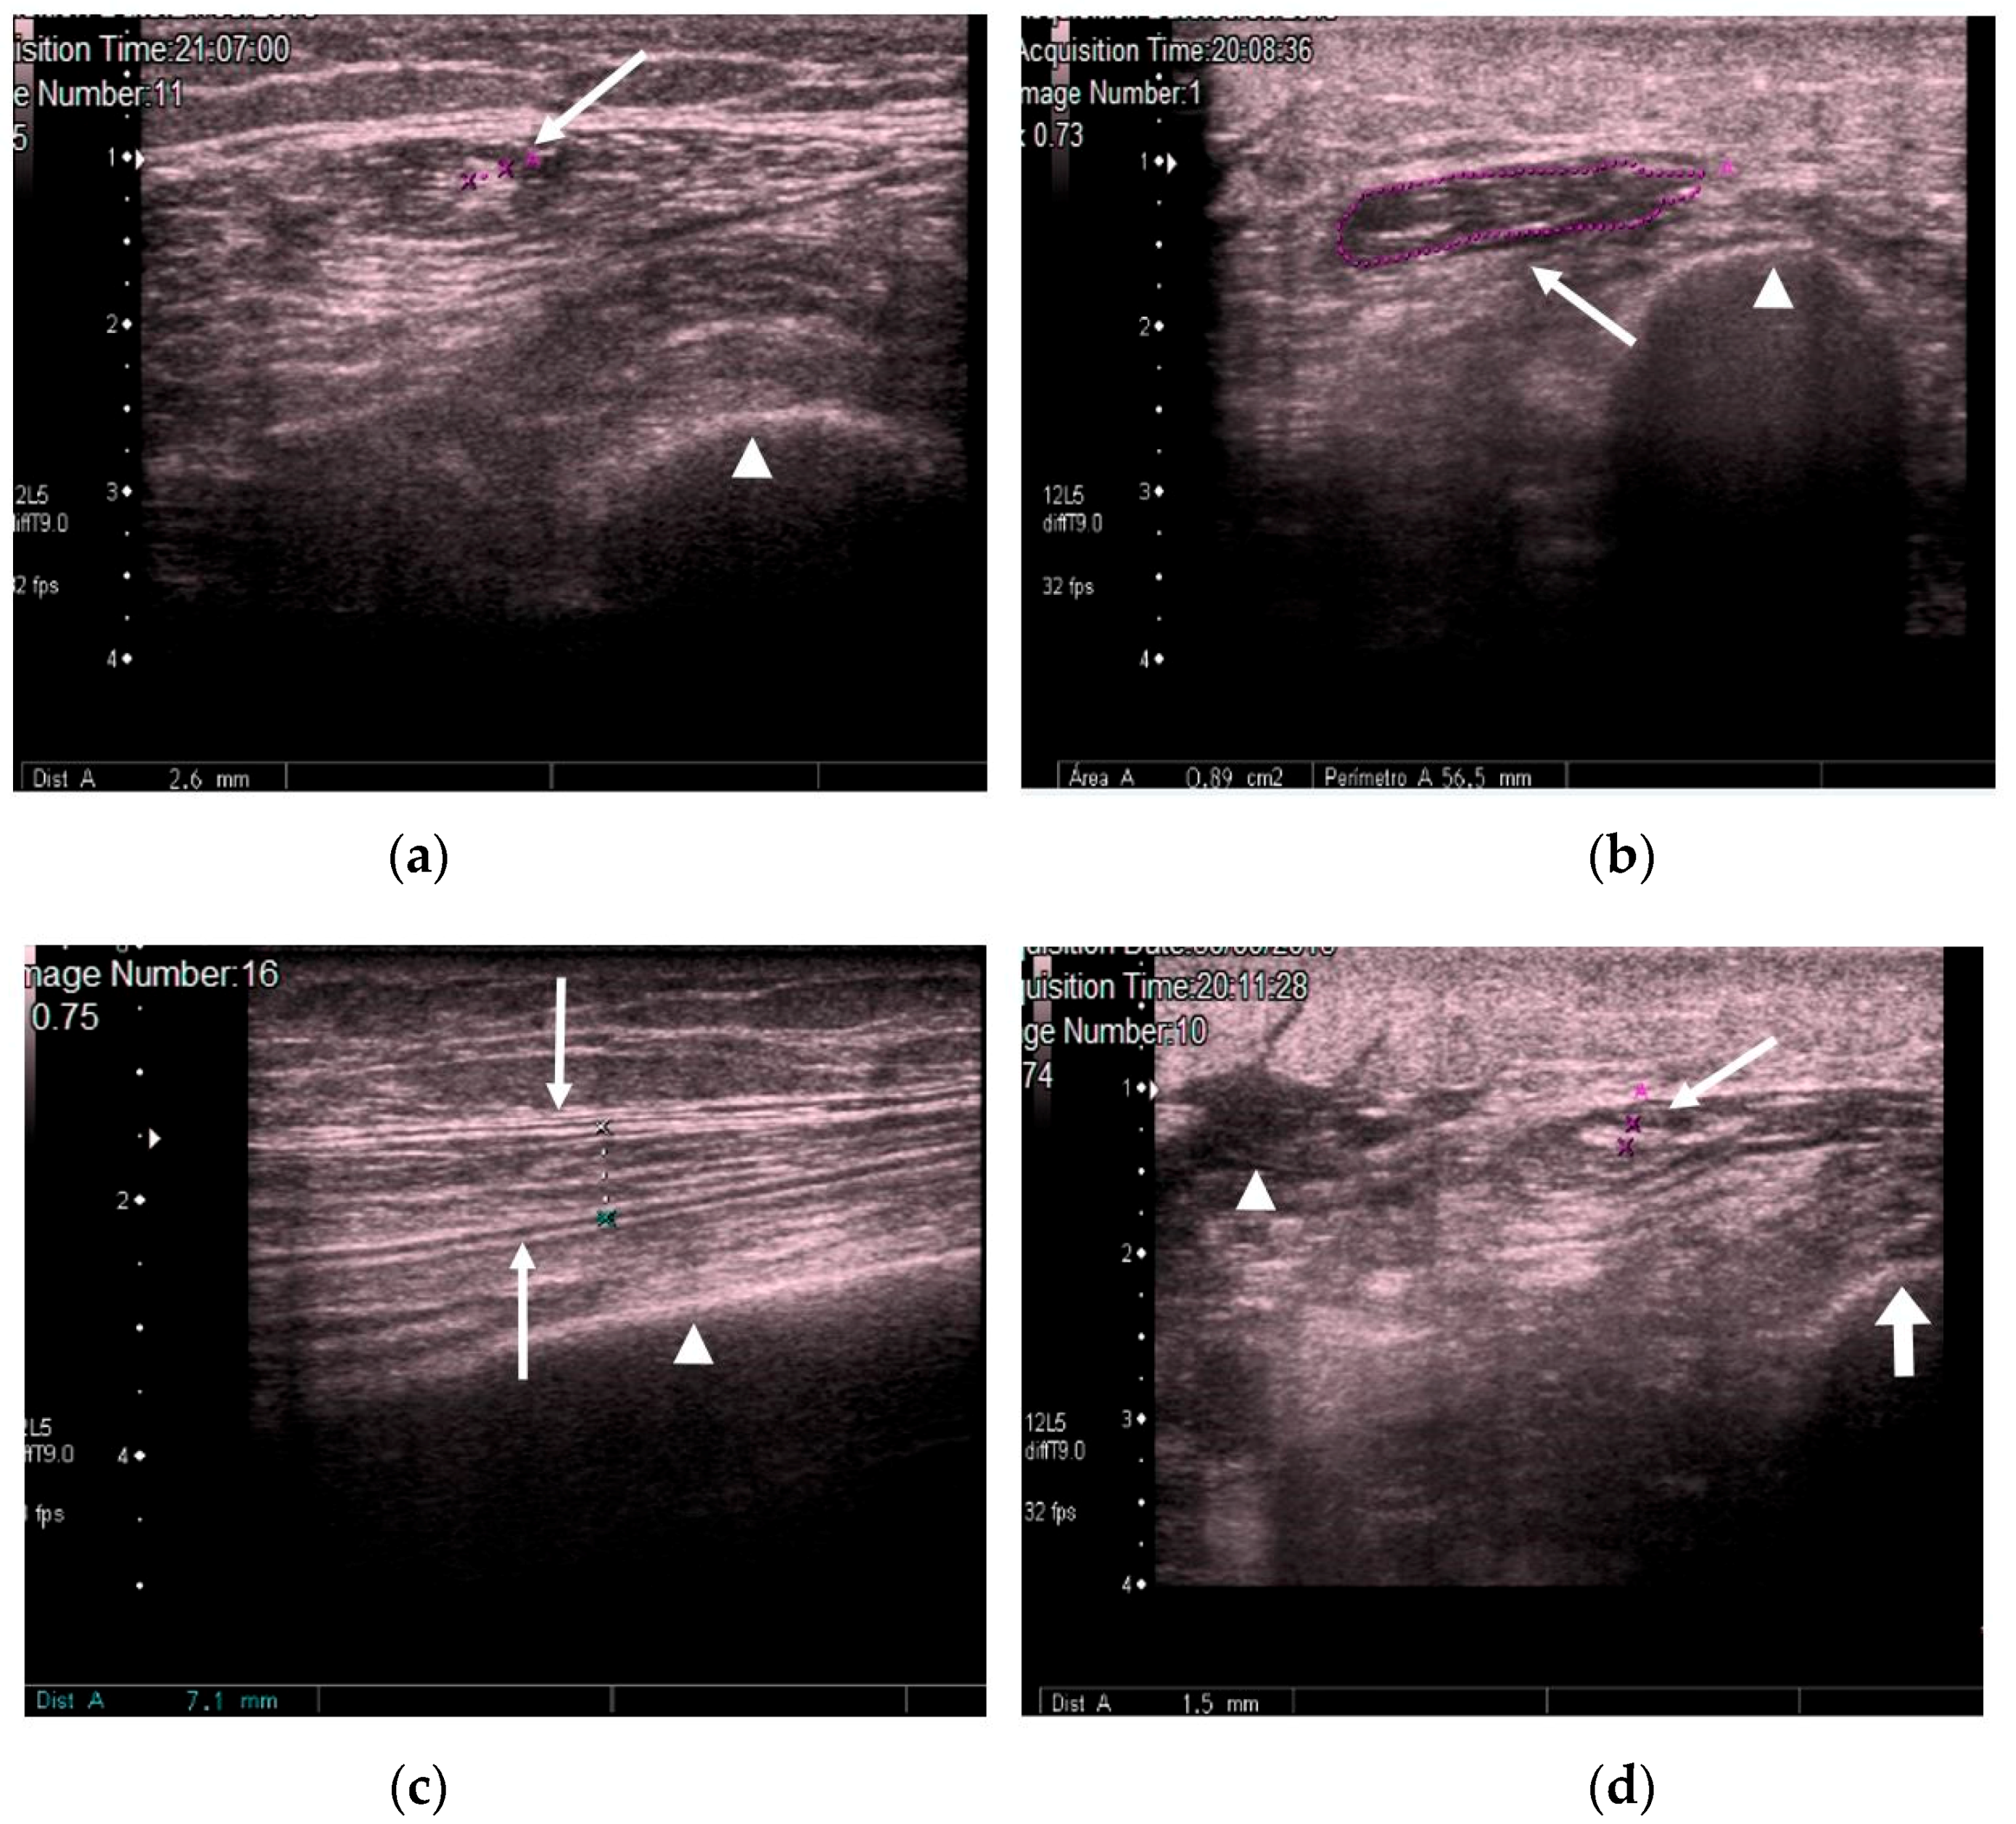

We measured the CSA in cm2 and muscle thickness in mm, and scanned for the presence or absence of edema in the subcutaneous cellular tissue and the intramuscular and intrafascial fluid (Figure 2).

Figure 2.

(a) Transversal QRF muscle US scan: multiorgan failure, tendon thickness of 2.6 mm (arrow), and femur (arrowhead). (b) Transversal QRF muscle US scan: multiorgan failure, cross-sectional area (CSA) of 0.89 cm2 (arrow), and femur (arrowhead). (c) Longitudinal QRF muscle US scan: muscle thickness of 7.1 mm (arrow) and femur (arrowhead). (d) Longitudinal QRF muscle US scan: subcutaneous edema, with intramuscular and interfacial fluid (arrowhead). QRF tendon is 1.5 mm (arrow) with the femur (thick arrow). QRF: quadriceps rectus femoris, US: ultrasound, CSA: cross-sectional area.